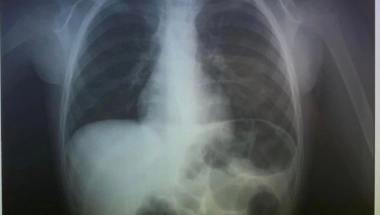

Doktori su prvo uradili rendgen, kako bi videli gde je završio novčić i videli da se zaglavio u grlu.

Doktori su na Fejsbuku objavili fotografije nakon intervencije.

"Oprostili smo se od 2023. godine hitnim vađenjem novčića koji je progutao dečak (4). Srećna Nova godina", napisali su oni.